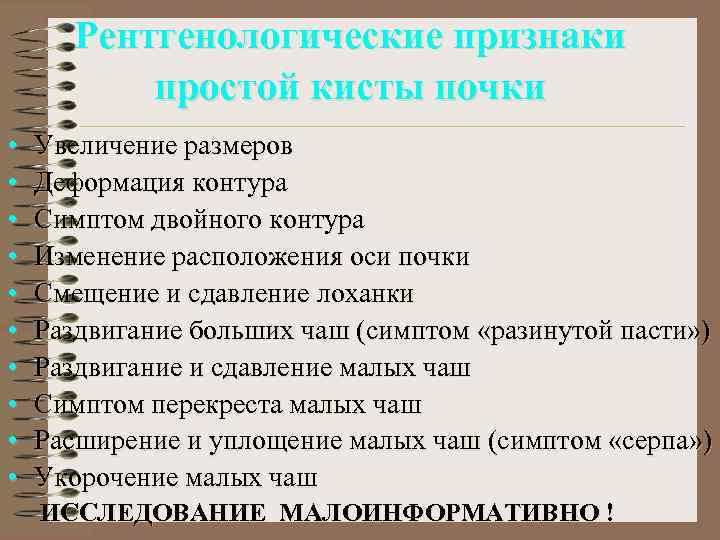

Рентгенологические признаки простой кисты почки • • • Увеличение размеров Деформация контура Симптом двойного контура Изменение расположения оси почки Смещение и сдавление лоханки Раздвигание больших чаш (симптом «разинутой пасти» ) Раздвигание и сдавление малых чаш Симптом перекреста малых чаш Расширение и уплощение малых чаш (симптом «серпа» ) Укорочение малых чаш ИССЛЕДОВАНИЕ МАЛОИНФОРМАТИВНО !